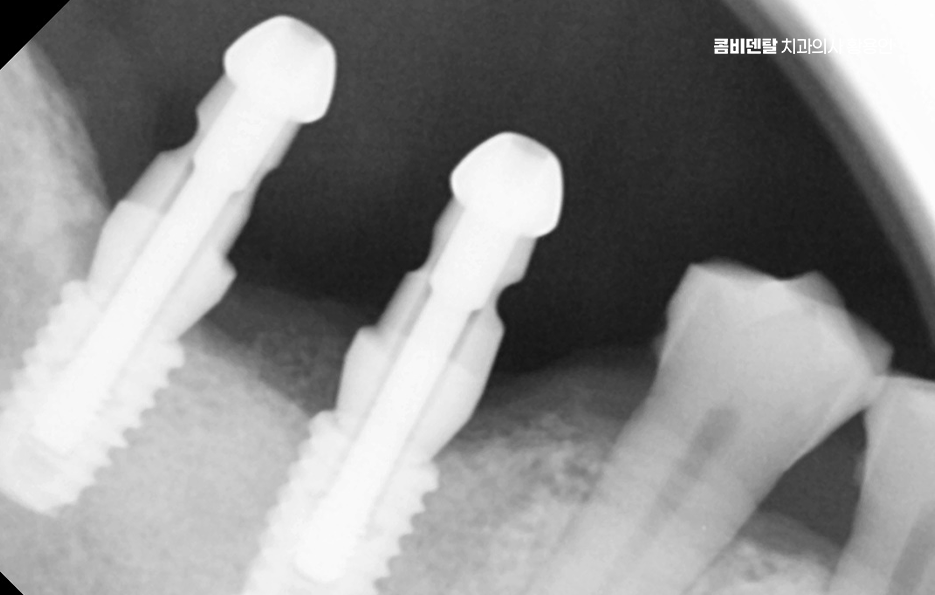

어금니 임플란트 과정에서 수술 당일에는 국소마취 후 잇몸을 절개하거나 최소 절개로 접근해 뼈에 임플란트를 식립하며 수술 후에는 일정 기간 골유착을 기다리는데 임플란트와 뼈가 단단히 결합하는 과정이라 할 수 있었어요

골유착이 완료되면 지대주를 연결하고 본을 떠서 최종 보철물을 제작하며 어금니 크라운은 강도와 교합 조화를 동시에 고려해 제작하는데 씹는 힘이 집중되는 부위이기 때문에 높이와 접촉점 조정이 중요하며 교합이 맞지 않으면 나사가 풀리거나 보철물에 문제가 생길 수 있어서 장착 후에도 교합 점검 및 정기적인 검진, 스케일링 등의 관리가 중요할 수 있어요